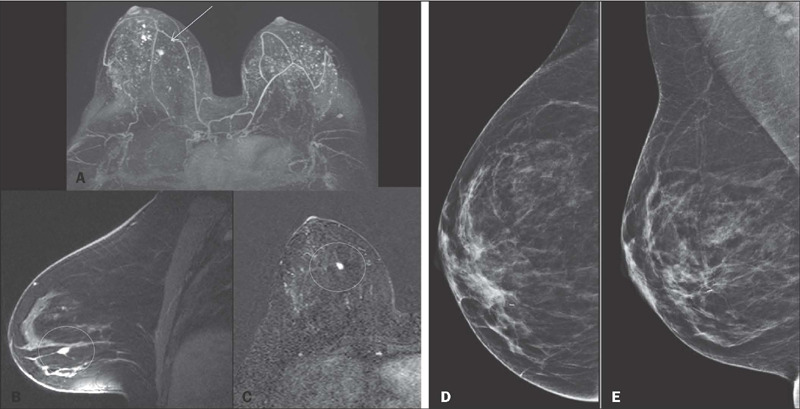

Results: We included 597 patients between 19 and 82 years of age. The main indications for MRI screening were a personal history of breast cancer, in 354 patients (59.3%), a family history of breast cancer, in 102 (17.1%), and a confirmed genetic mutation, in 67 (11.2%). The MRI result was classified, in accordance with the categories defined in the Breast Imaging Reporting and Data System, as benign (category 1 or 2), in 425 patients (71.2%), probably benign (category 3), in 143 (24.0%), or suspicious (category 4 or 5), in 29 (4.9%). On MRI, 11 malignant tumors were identified, all of which were invasive carcinomas. Among those 11 carcinomas, six (54.5%) were categorized as minimal cancers (< 1 cm), and the axillary lymph nodes were negative in 10 (90.9%). The cancer detection rate was 18.4/1,000 examinations, and the positive predictive value for suspicious lesions submitted to biopsy was 37.9%.

Conclusion: In our sample, the main indication for breast MRI screening was a personal history of breast cancer. The results indicate that MRI is a highly accurate method for the early detection of breast neoplasms in this population.